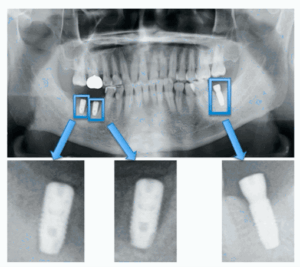

ولتحسين دقة التخطيط لزراعة الأسنان، تناولت دراسة “تصنيف أنظمة زرع الأسنان باستخدام التعلم العميق” خوارزمية (VGG-16)لتحديد 12 نوعاً من زرعات الأسنان المجهولة في صور الأشعة بدقة 95%، مما يسهل عملية التعرف عليها وصيانة التركيبات مستقبلاً [16].

الشكل [6]: اقتصاص صور الزرع السني لعزل كل غرسة على حدة [16]